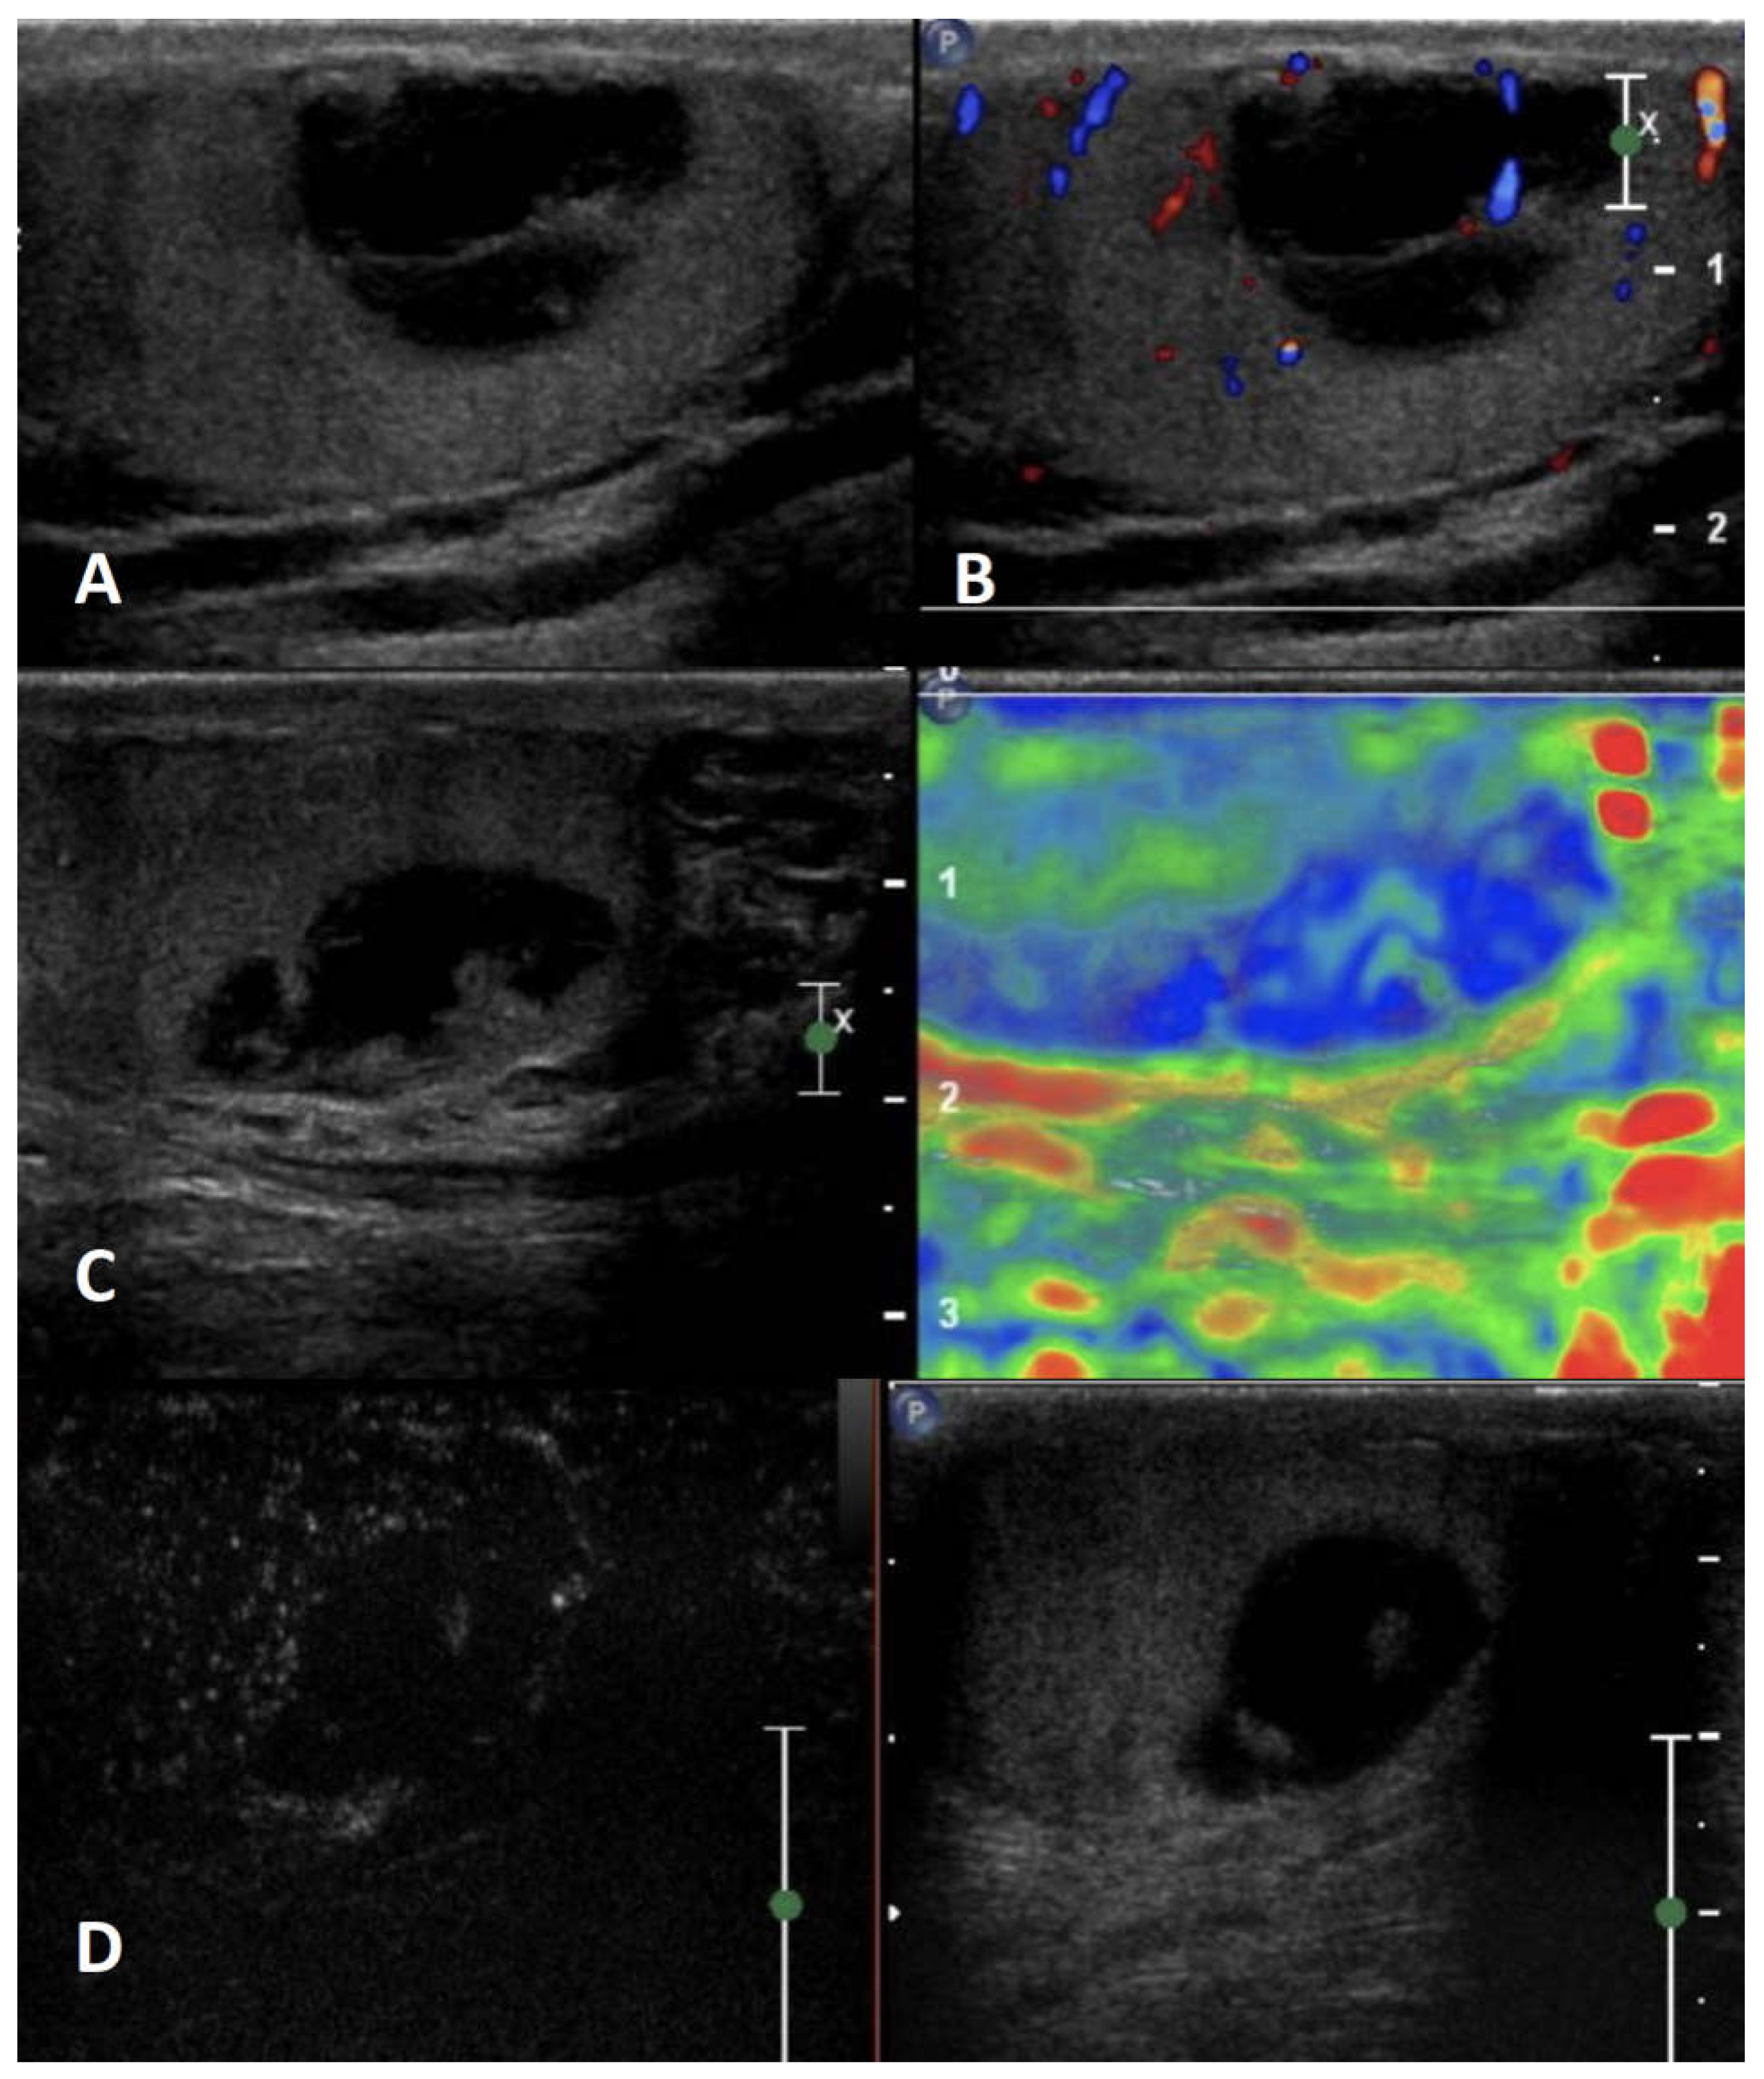

5.1. Intratesticular cysts

5.2. Epidermoid cysts

| Non-neoplastic intratesticular lesions | |||||

| Clinical presentation | GSUS | CDUS | CEUS | SE | |

| Simple cyst | asymptomatic/ incidental finding, usually not palpable |

rounded anechoic lesions with thin, clear, hyperechoic wall and posterior acoustic enhancement | avascular | unenhanced | soft lesion with high elastic strain |

| Epidermoid cyst | asymptomatic/ can be palpable |

well circumscribed rounded lesion with “onion ring” aspect (concentric hypo- and hyper-echoic rings) OR densely calcified mass with acoustic shadow OR cyst with hypoechoic rim and central calcification OR mixed atypical pattern | avascular | unenhanced/ perilesional rim enhancement |

hard lesion with low/absent elastic strain |